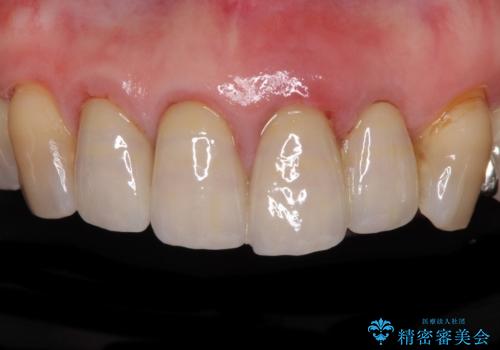

折れてしまった前歯 インプラントによる補綴治療